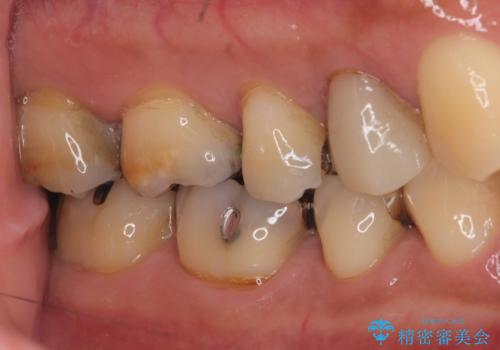

虫歯を除去後、フルジルコニアクラウンで治療を行いました。

- 99,000円(税込)フルジルコニアクラウン8.8万円+仮歯1.1万円費用は治療当時の料金となります

不適合な銀歯を外して、虫歯の除去後にシリコンで印象をとりフルジルコニアクラウンで治療を行いました。